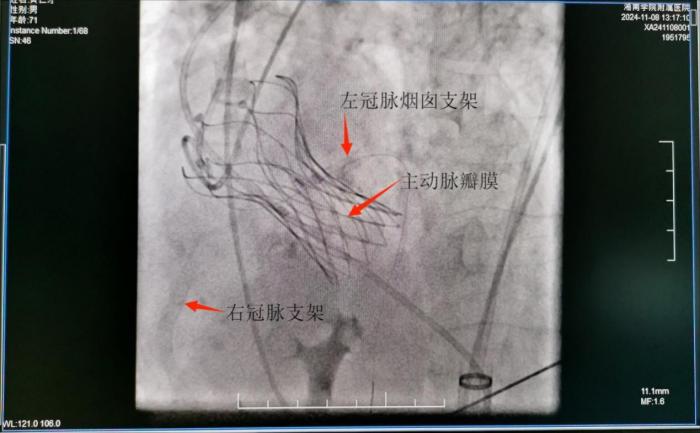

本网讯(通讯员 李虎)近日,湘南学院附属医院多学科专家密切配合,成功为一名主动脉瓣膜重度狭窄的老年患者实施了“经皮右冠状动脉支架置入术+左冠状动脉烟囱支架技术+经导管主动脉瓣膜置换术”,标志着该院心血管内科专业再次取得重大突破。

为保证手术的顺利进行,医院心外科、麻醉科、神经内科、医学影像科以及超声科在内的TAVR团队,多方联动,助力手术成功开展。术中予右冠脉置入了冠脉支架、左冠脉置入了烟囱支架,通过股动脉将人工主动脉瓣膜输送至主动脉瓣区打开,从而完成人工主动脉瓣膜置入,顺利恢复瓣膜功能。